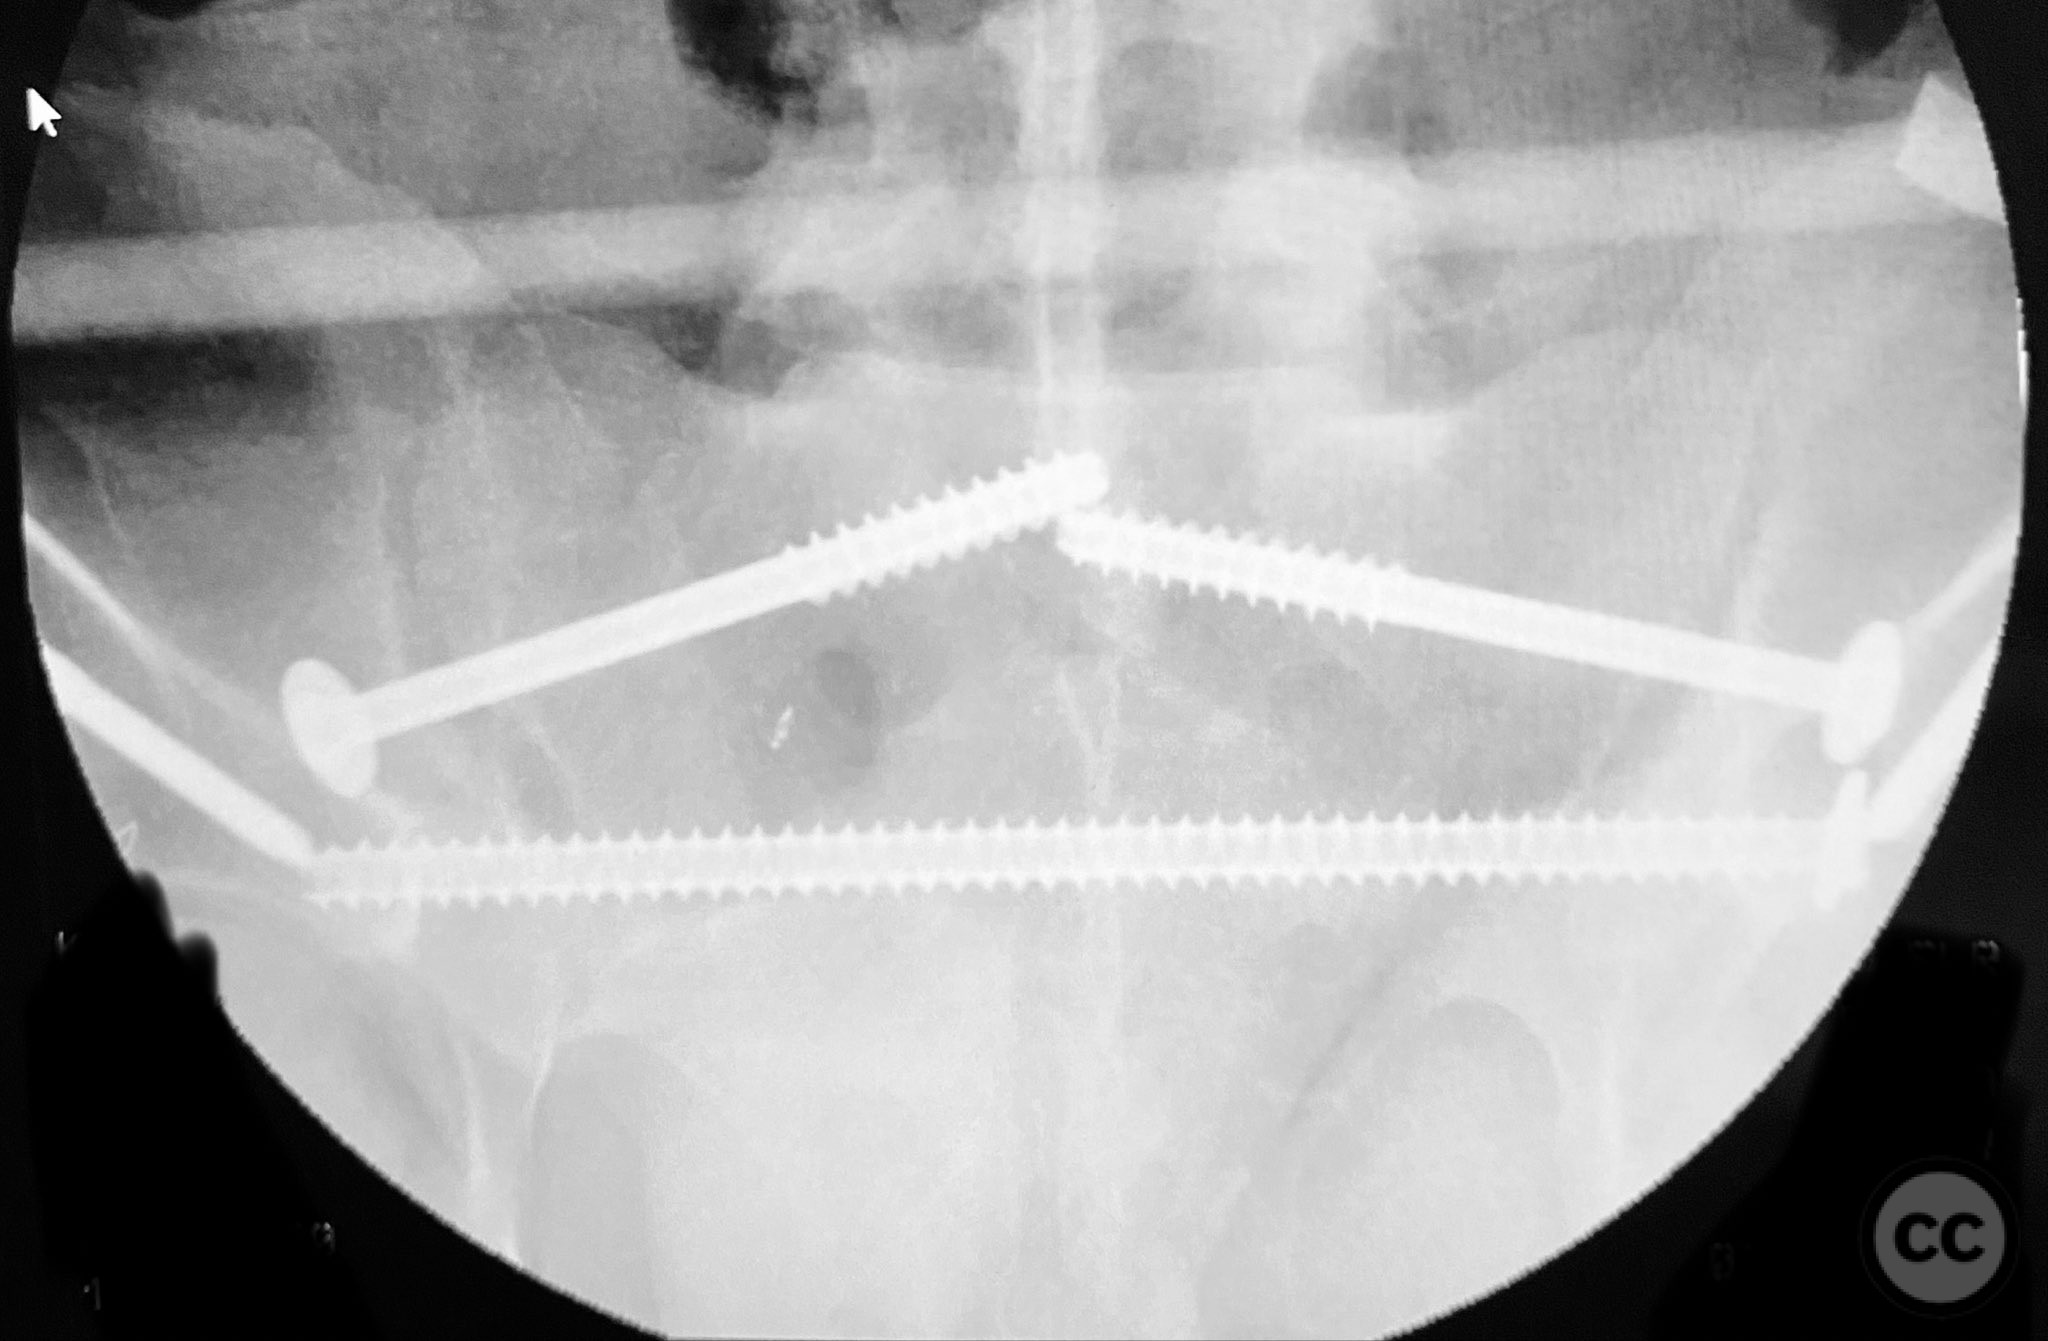

Operative remarks:

Initial reduction of the posterior column was attempted using a Jungbluth clamp; however, intraoperative fluoroscopy revealed suboptimal reduction despite satisfactory direct visualization. A perpendicular reduction clamp was then applied, resulting in improved alignment as confirmed by fluoroscopy. The transverse acetabular fracture was stabilized with two 4.5 mm cortical screws placed across the fracture line, followed by application of posterior column plates for additional stability. The symphyseal disruption was managed non-operatively without direct stabilization.